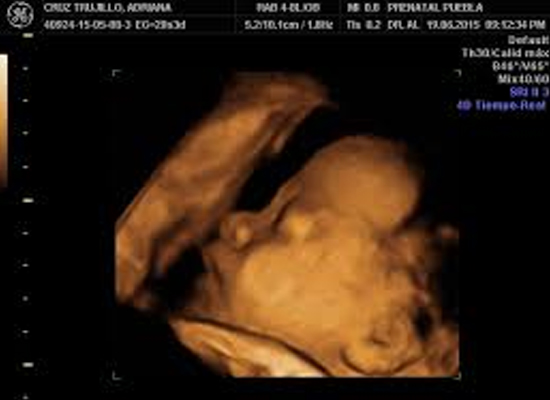

Contamos con equipos de ultrasonido de alto desempeño y resolución de imagen. Con capacidad de realizar estudios de 4 D y elastografia, realizamos todos los estudios de ultrasonido como son:

• Ultrasonido Ginegco-Obstetricia (ultrasonido estructural de embarazo, ultrasonido vagina, ultrasonido de ovarios y útero, etc.)

• Ultrasonido estructural semana 11-14 de embarazo